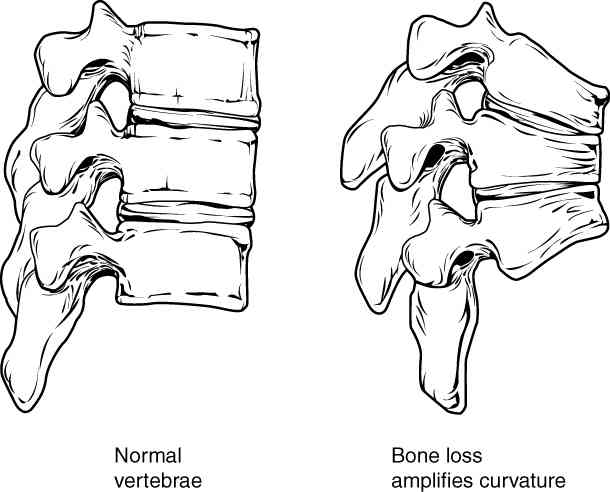

This page is under construction. For now, it is just a resource of the images found in the OpenStax Anatomy and Physiology Handbook. It wil slowly change into a revision tool. Each slide has a number. Use this to refer to the slide. When completed, it will have an unlabelled section, with labelled slides in parallel. On the unlabelled slides, write your answer and use the labelled slide to assess yourself. Keep track by also noting the number on each slide. Improvement at each attempt is important, more so than full marks on a first attempt.